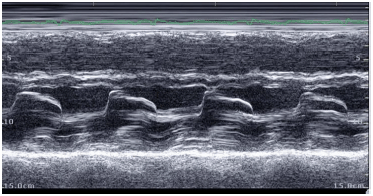

Assinale a classificação de Carpentier para a imagem abaixo.